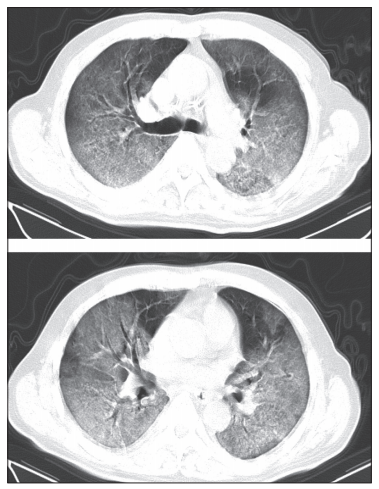

实际上,研究团队也着重关注了有既往病史的患者。下图是一名患有慢性肺病(结核病)、入院第 12 天因呼吸窘迫症去世的 60 岁男性患者的不同级别的 CT 影像。根据其发病第 8 天的 CT 影像,两肺可见广泛的磨玻璃影,几乎累及整个下叶、大部分上叶和右肺中叶,“白肺”(肺部显影呈一大片的白色状,一般是肺部被炎症所侵润的表现),并伴有空气支气管造影。